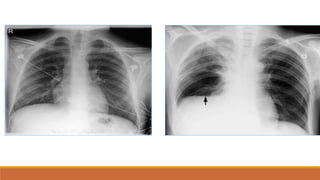

TDMP TỰ DO

PHIM THẲNG ĐỨNG

•TÙ GÓC SƯỜN HOÀNH

•BÓNG MỜ VÙNG THẤP XÓA BỜ VÒM HOÀNH VỚI

GIỚI HẠN TRÊN LÀ ĐƯỜNG CONG DAMOISEAU

•ĐẨY TRUNG THẤT VỀ PHÍA ĐỐIDIỆN

•XẸP PHỔI THỤ ĐỘNG (+/-)

•THAY ĐỔI THEO TƯ THẾ

PHIM NGHIÊNG

•TÙ GÓC SƯỜN HOÀNH TRƯỚC VÀ SAU

•BÓNG MỜ VÙNG THẤP VỚI GIỚI HẠN TRÊN LÀ

ĐƯỜNG CONG LÕM XUỐNG DƯỚI

TDMP lượng ít

TDMP lượng vừa

TDMP lượng nhiều

TDMP ÁP LỰC, ĐẨY TRUNG THẤT VỀ PHÍA ĐỐIDIỆN